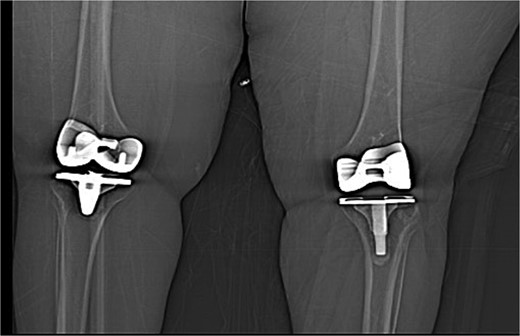

Upon examination in the emergency room, the patient was vitally stable, alert, and oriented. Her skin was intact, showing a healed wound. Mild swelling was noted over the left knee joint, with no erythema or ecchymosis. She had tenderness over the medial surface of the knee. The active ROM was from 0º to 90º and was limited due to pain; the passive ROM was from 0º to 110º with a clicking sound during flexion. Soft compartments were noted, and distal neurovascular examination was unremarkable (Fig. 2).

(A) Anteroposterior view of the left knee in the emergency department. (B) Lateral view of the left knee in the emergency department.